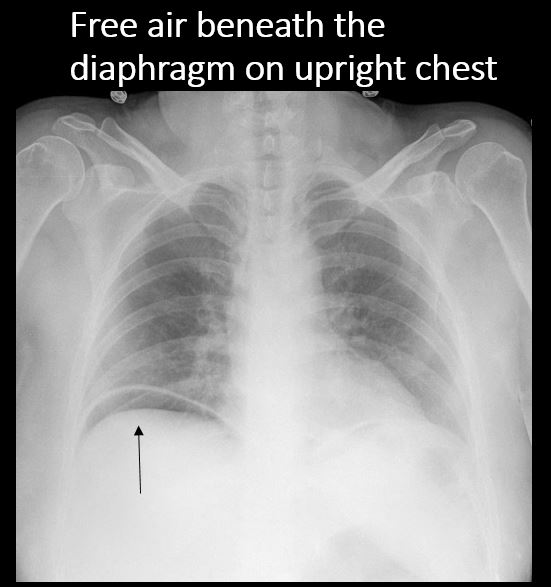

The upright view of the chest includes the diaphragm. |

There is free air beneath the diaphragm. |

No | NA |